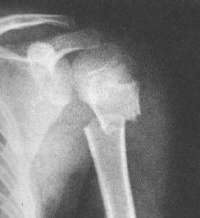

Bka36.jpg

肱骨外科颈位于解剖颈下方2~3cm,是肱骨头松质骨和肱骨干皮质骨交界的部位,很易发生骨折。各种年龄均可发生,老年人较多。

手或肘部着地摔伤史或肩部直接暴力击伤史,肩部疼痛,活动加重。X 线片可确诊,且可显示骨折类型及移位情况。

1.内收或外展型损伤:最常见。X线正位片所见骨折线为横行,骨折轻度向内或向外成角,远折端呈内收或外展状态。侧位片上均无明显向前或向后成角、错位改变。肱骨外科颈骨折常合并骨大结节骨折,表现为撕脱的蝶形骨折片。